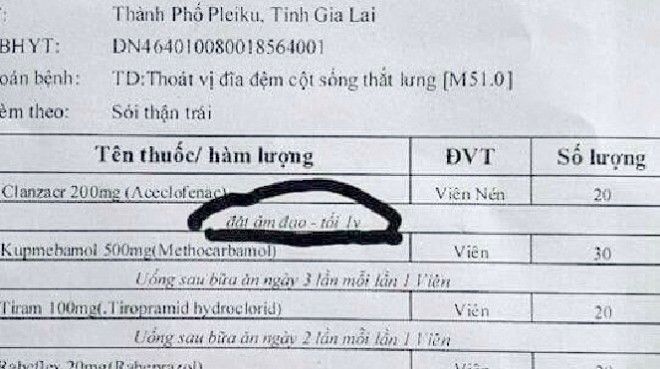

Nam bệnh nhân được bác sỹ kê đơn thuốc đặt vào…âm đạo